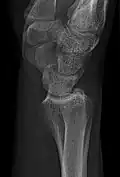

- Wrist - DP and Lateral

-

Left wrist by dorsoplantar projection -

Lateral projection